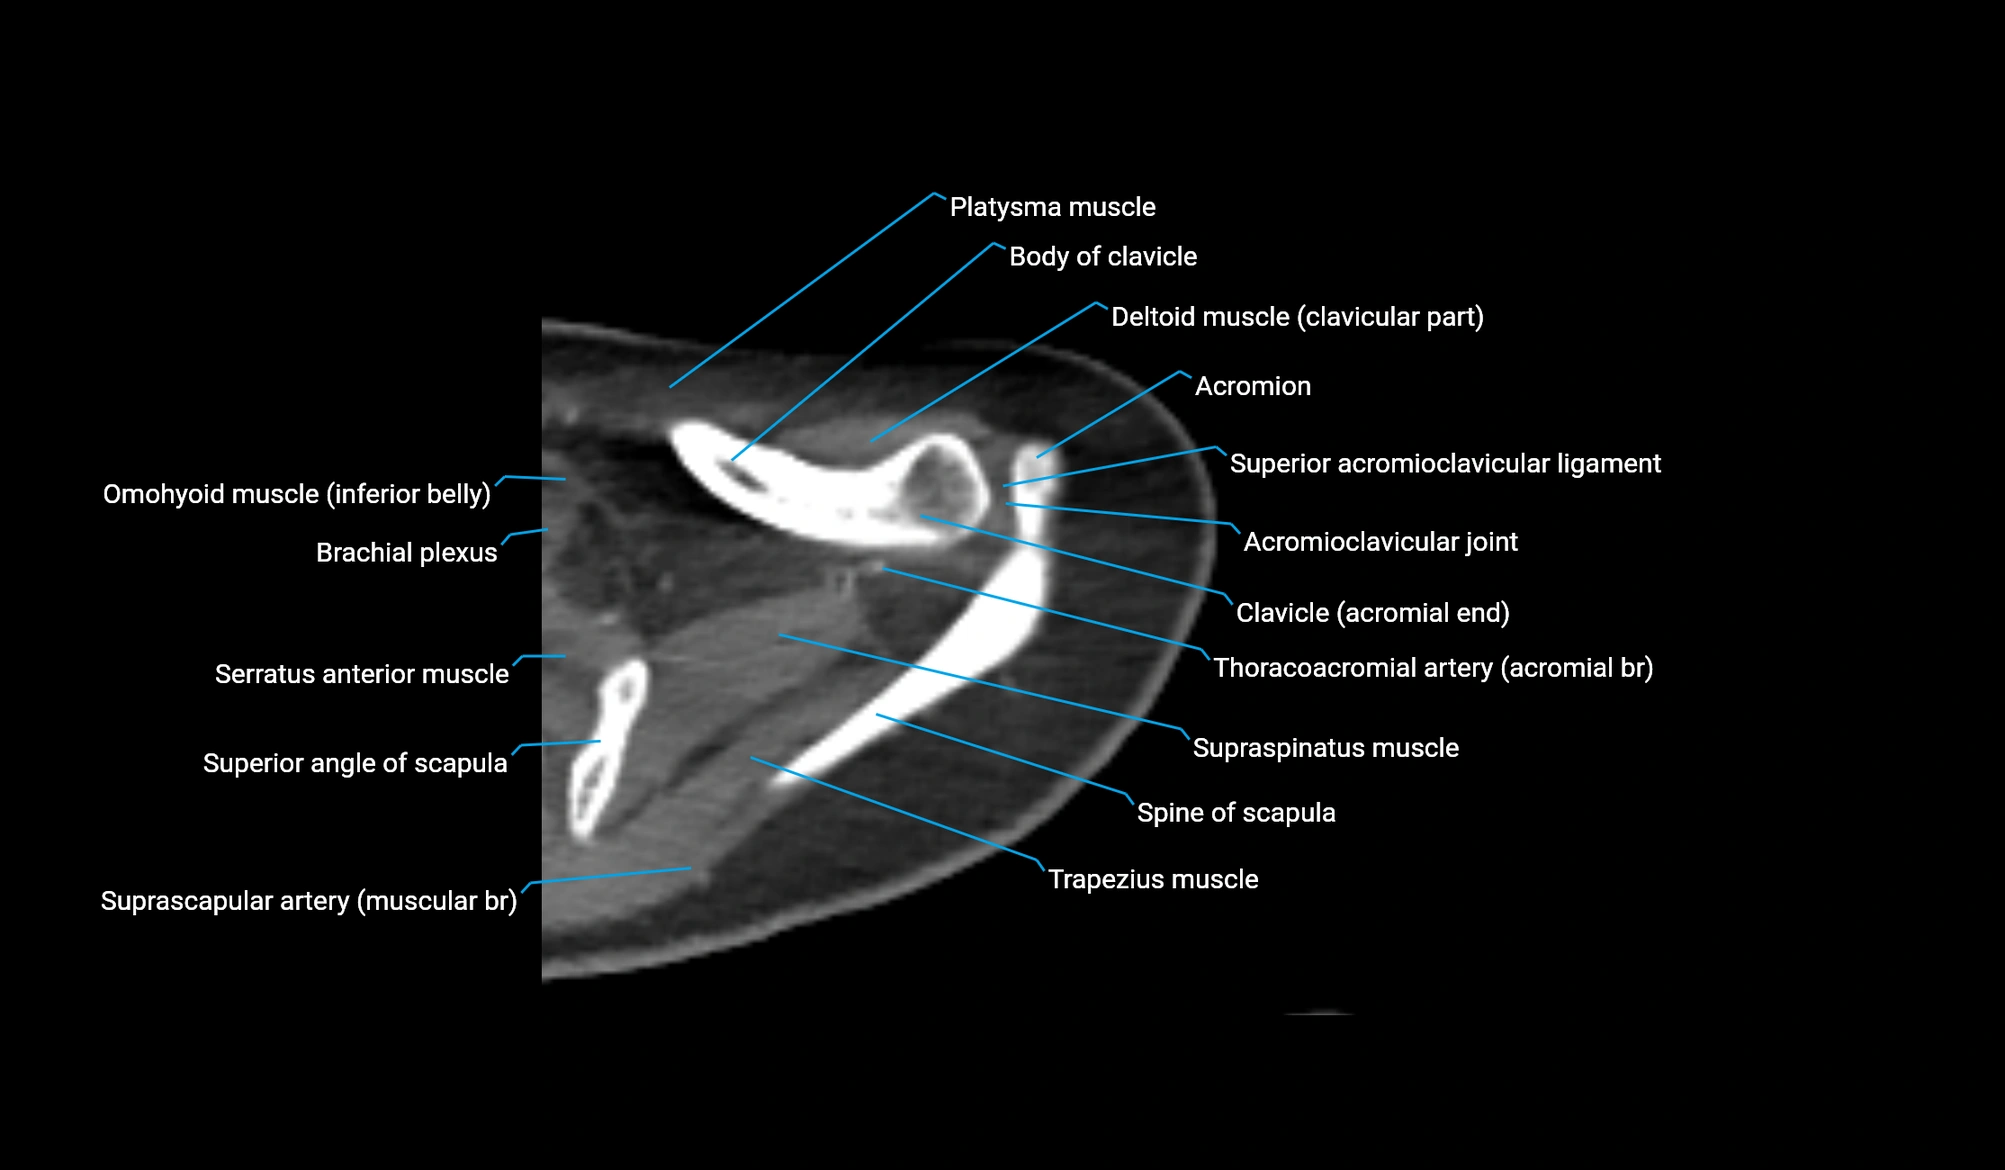

- Acromioclavicular joint

- Acromioclavicular ligament

- Acromion process of scapula

- Brachial plexus

- Clavicular part of deltoid muscle

- Inferior belly of omohyoid muscle

- Shaft (body) of clavicle

- Spine of scapula

- Superior acromioclavicular ligament

- Superior angle of scapula

- Supraspinatus muscle